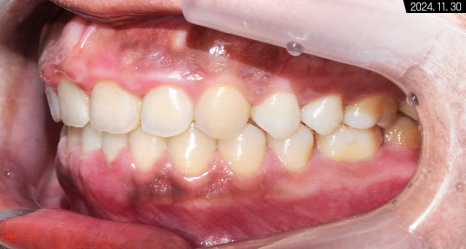

구내 사진으로 측절치 잇몸에서

피가 나오는 것을 볼 수 있는데요.

이는 치주낭이 깊음에 따라

치근 소파술을 동반하는 과정에서 생긴 현상입니다.

출혈이 약간 있지만

잇몸이 좋아지는 과정이기 때문에

걱정하지 않으셔도 됩니다.

어금니 수평 관계도 좋고 정출된 곳 없이

정상 라인 안에 치아가 모두

들어온 것을 확인할 수 있습니다.